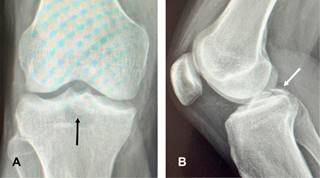

La fractura por avulsión del ligamento cruzado posterior (LCP) representa la lesión aislada más común del LCP (~ 50%), implicando la separación de la inserción tibial posterior del LCP en grados variables. Estos traumatismos se observan comúnmente en accidentes de motocicleta o automovilísticos (lesiones en Tableros de instrumentos) en los que se producen fuerzas de posteriorización contra la tibia en una rodilla flexionada. También se observan en individuos que saltan y aterrizan sobre un pie en flexión plantar mientras la rodilla está flexionada, en el contexto deportivo (esencialmente colocando la tibia bajo una fuerza de posteriorización). Se les clasifica en tipo I: cuando el fragmento óseo no está desplazado; tipo II: existe desplazamiento hacia arriba de la cara posterior del fragmento de hueso tibial avulsionado; y tipo III: cuando el fragmento óseo avulsionado está totalmente desplazado. Clínicamente existe signo del cajón posterior. Radiográficamente, en la placa lateral se identifica discontinuidad ósea en la superficie articular tibial posterior (Figura 1). En la resonancia magnética o la tomografía computarizada, se puede observar un fragmento de hueso fracturado unido al LCP retraído (Figura 2). El diagnóstico diferencial incluye desgarro del LCP. El tratamiento es la reinserción quirúrgica del fragmento avulsionado (Figura 3).

Figura 1: Radiografías de rodilla derecha anteroposterior (A) y lateral (B), en esta última se muestra discontinuidad ósea en la superficie posterior articular tibial (flechas).